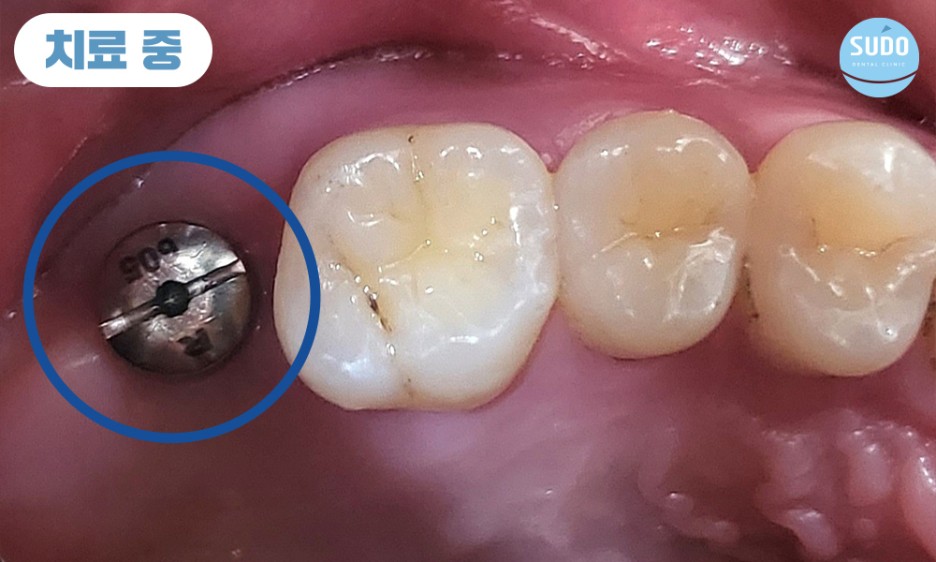

기존의 보철물 제거하고 보니, 이미 뿌리까지 충치가 많이 진행된 상태로 살려서 쓰기 힘들 것이라 판단되어 당일 발치 후 임플란트 진행 계획을 수립하였습니다.

식립 당일 힐링 어버트먼트를 결합한 채로 본래의 잇몸뼈와 안정적으로 융합될 수 있도록 충분한 기간 동안 기다려주었습니다.

힐링 어버트먼트란, 임플란트를 보호하고 잇몸 조직의 적절한 치료를 촉진하며 미관을 개선하고 최종 보철물의 배치를 위한 안정적인 기준을 제공하기 위한 목적으로 사용합니다.